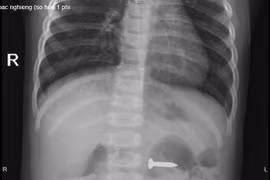

Kịp thời gắp đinh vít sắc nhọn trong dạ dày bé gái 2 tuổi

(GLO)- Ngày 14-12, Bệnh viện Sản Nhi tỉnh Phú Thọ cho biết, các bác sĩ khoa Cấp cứu đã tiếp nhận và kịp thời gắp 1 chiếc đinh vít sắc nhọn trong dạ dày bé N.P.C. (2 tuổi, trú tại huyện Lập Thạch, tỉnh Vĩnh Phúc).